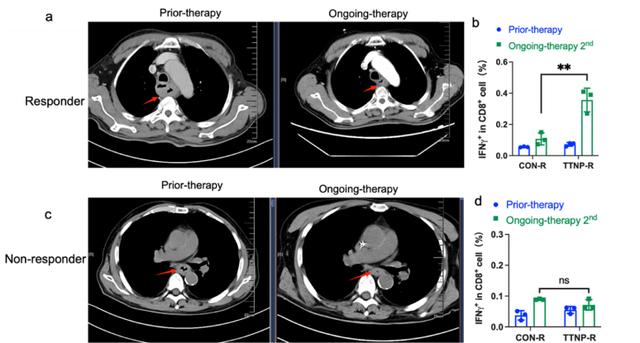

根据研究结果,癌症患者外周血中的 ETAST 含量显著高于健康人外周血中的 ETAST 含量。而且,治疗效果与癌症患者外周血中的 ETAST 含量呈正相关。

也就是说,只有当免疫治疗有效时,癌症患者外周血中的 ETAST 含量才会上升,单细胞测序结果也证实了这一结论。

图丨非小细胞肺癌患者免疫治疗疗效与外周血中肿瘤抗原特异性 T 细胞含量正相关(来源:Advanced Science)